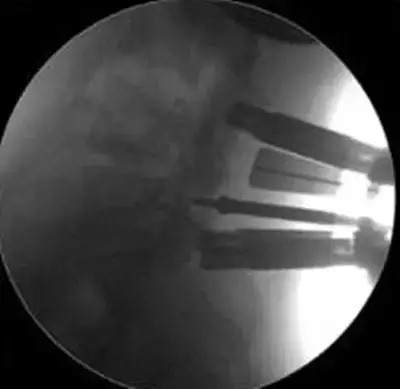

劉志安副院長所說的“微創(chuàng)小切口”就是通道下髓核摘除植骨融合經(jīng)皮內(nèi)固定術(shù)。其原理就是利用MIS-TLIF技術(shù)微創(chuàng)治療腰椎疾病,不但能達(dá)到開放手術(shù)的效果,且切口及創(chuàng)傷為開放切口的1/3,術(shù)中出血量少,患者術(shù)后可以恢復(fù)更快。

據(jù)劉院長介紹,MIS-TLIF技術(shù)是經(jīng)椎旁肌間隙入路運用脊柱內(nèi)鏡或?qū)S猛ǖ佬醒甸g盤切除、椎管減壓、植骨內(nèi)固定術(shù),是一項應(yīng)用廣泛、技術(shù)成熟的脊柱微創(chuàng)手術(shù)方法。本技術(shù)可以完成與傳統(tǒng)手術(shù)完全相同的椎間盤切除、椎間植骨融合內(nèi)固定等操作。手術(shù)切口一般3-5厘米,本手術(shù)方式可有效避免傳統(tǒng)手術(shù)對腰背肌肉的損傷,患者術(shù)后腰背部疼痛輕、恢復(fù)快,手術(shù)效果優(yōu)于傳統(tǒng)手術(shù),治療后1-3天即可下床活動。本技術(shù)適于大部分的腰椎間盤突出癥、腰椎管狹窄癥、腰椎滑脫癥等。